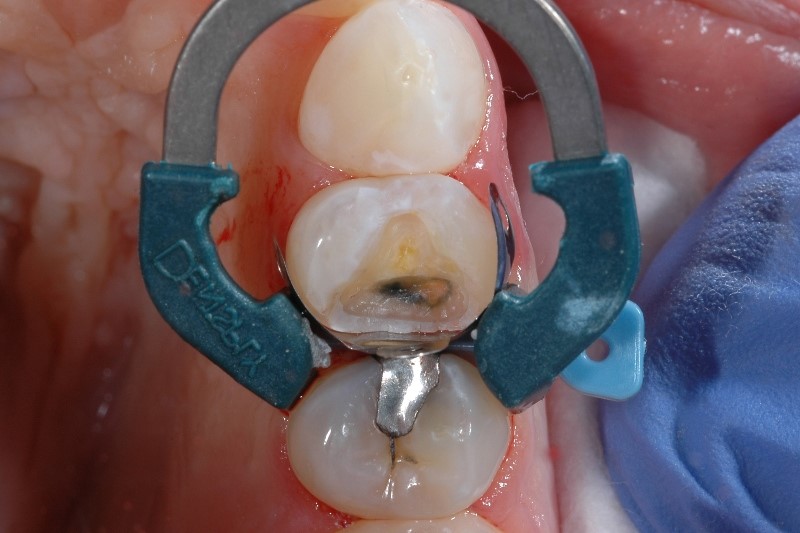

Sensibilidad causada por aislamiento de dientes inadecuado

El aislamiento de dientes adecuado es clave en cualquier fase de la restauración de clase II, ya que evita que la saliva y la sangre contaminen el campo restaurador. Si el campo restaurador se contamina, las propiedades físicas y el éxito final de la restauración pueden verse comprometidos y provocar sensibilidad posoperatoria y molestia en el paciente.

Cómo evitar la sensibilidad causada por el aislamiento de dientes inadecuado

Si tiene problemas con el aislamiento, no está solo: el 97 % de los médicos dice que lograr el aislamiento adecuado de una cavidad de clase II es difícil en al menos 1 de cada 10 casos.2 Además de las medidas comunes de aislamiento, considere la importancia de una matriz bien adaptada. El uso de sistemas de matriz desarrollados específicamente para colocar materiales de composite, como nuestro sistema de matriz seccional Palodent® V3 , ayuda a lograr un sellado hermético en el margen gingival.